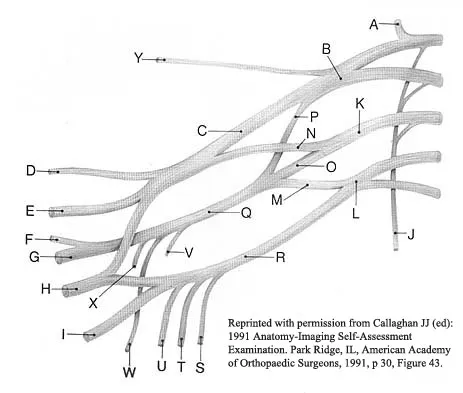

Question 50

A patient who sustained a knife wound to the axilla 4 months ago now has profound interosseous wasting and generalized hand weakness. A brachial plexus injury is likely at which of the following locations in Figure 29?

Explanation